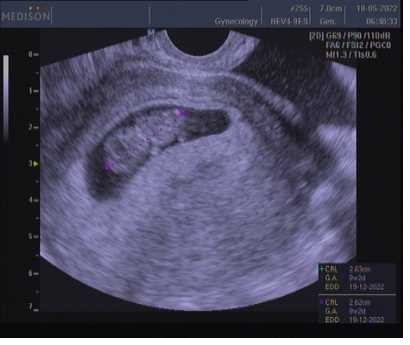

@vero987nika prvni fotka začátek 10tt druhá fotka 4tt